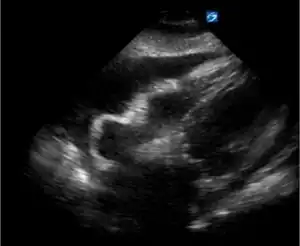

| Transthoracic echocardiogram in the four-chamber apical view-pericardial effusion with right atrial and right ventricular inversion | |

Ventricular inversion is a condition in which the anatomic right ventricle of the heart is on the left side of the interventricular septum and the anatomic left ventricle is on the right.[1]